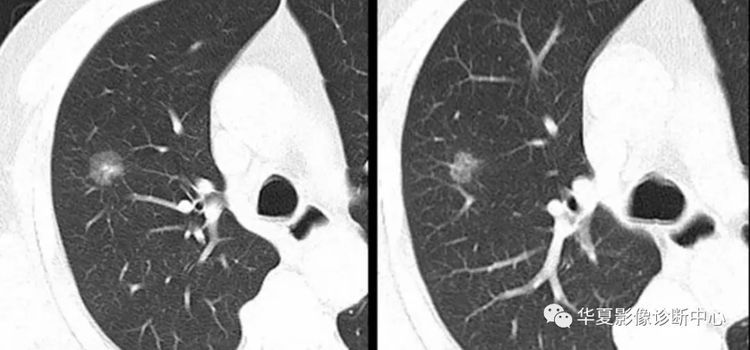

双肺出现的多个转移病灶

颅内出现的多个转移病灶